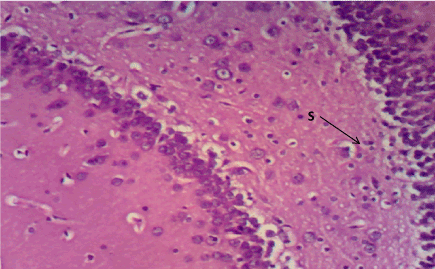

Haematoxylin & Eosin: The Normal control group (Figure 6) shows normal neuronal cells with distinctive cell layers, Diabetic control group (figure 7) shows increased pericellular spaces and chromatolysis signifying neuronal cell damage or neurodegeneration, Z. officinale treated diabetic group (Day 14) (Figure 8) shows restoration of neuronal cells with distinctive characteristic cell layers, Z. officinale treated diabetic group (Day 21) (Figure 9) shows restoration of neuronal cells with neuronal cell and layers and Metformin treated diabetic group (Figure 10) shows partial restoration of neuronal cells cell layers [7].

Figure 8. Photomicrograph of the hippocampus of Group C, preserved cell layer (S). (H&E) X100

Hippocampus: The hippocampus forms part of the limbic system and functions majorly in long-term memory and spatial navigation. Damage in any cell in the hippocampus can cause gross effects on the learning process of the individual. Astrocytes are most numerous glial cells in the brain and they help in the filling of spaces forming glial scars caused by neuronal damage and also help to repair the damaged cells that cannot be regenerated and a reduction in the number of these glial cells that help keep neuronal cells connected will cause a deficit in cell to cell connection. Figure 16 shows the normal hippocampus showing the different cell layers with no neuronal injury which is in support with the biochemical findings on free radicals and antioxidants. Figure 7 (Diabetic control) as compared to figure 6 (normal control) shows neuronal injury which was prominent throughout the granular layer which is in support with the biochemical analysis done on free radicals and antioxidants which shows elevated levels of free radicals and reduced levels of antioxidants proving low defence against free radicals which caused an increase in neurodegeneration and this was evident in the behavioural study. Diabetic control (Figure 11) shows degenerated pyramidal cells with short and disconnected processes and also has very few astrocytes with pericidal spaces. Figure 12 and figure 13 (Diabetes+ Z. officinale 14 and day 21) showed well preserved pyramidal cells in both groups. Figure 13 shows preserved neuronal cells as compared to that of figure 11, the astrocytes seen in figure 12 were numerous compared to that of the other groups which confirms the neuroprotective effect of Z. Officinale on brain cell and this finding is in agreement with, which observed that the administration of Z. officinale to diabetic rats increased astroglial response to injury which improved neurogenesis [9].